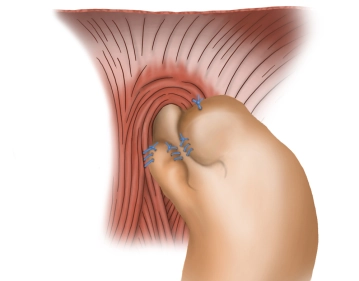

Präparation des unteren Ösophagus

Toneinstellungen Man geht nun weit ins untere Mediastinum hinein und löst den unteren Ösophagus zirkulär aus seinen Verklebungen heraus. Dabei wird der hintere Vagusnerv eindeutig identifiziert und verbleibt an der Ösophagusmuskulatur. Der Ösophagus wird so weit aus dem Mediastinum heraus gelöst, bis der Bereich des unteren Ösophagussphinkters spannungsfrei im Bauchraum zu liegen kommt.